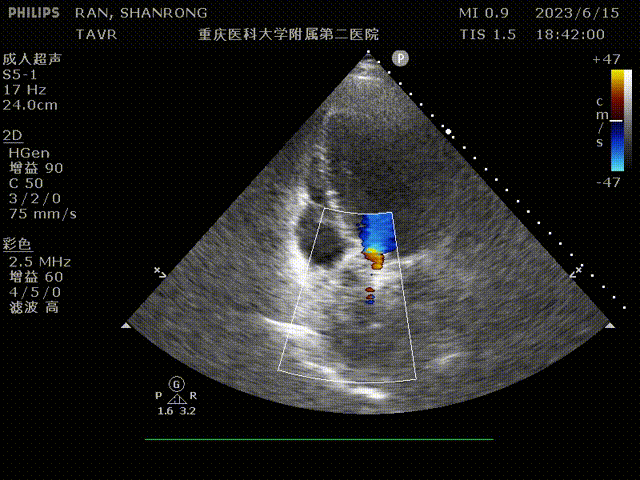

心脏彩超